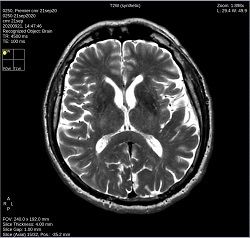

Click T2W to change the image contrast to synthetic T2-weighted.

Click PDW to change the image contrast to PD-weighted synthetic.